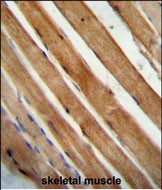

The SLC25A12 (N-Term) antibody is a specialized tool used to detect the N-terminal region of the solute carrier family 25 member 12 (SLC25A12) protein, also known as aralar1. SLC25A12 encodes a calcium-binding mitochondrial carrier protein localized in the inner mitochondrial membrane. It functions as an aspartate/glutamate exchanger, playing a critical role in the malate-aspartate shuttle, which facilitates the transfer of reducing equivalents into mitochondria for ATP production and supports cytosolic NAD⁺ regeneration. This protein is highly expressed in the brain, skeletal muscle, and heart, and is implicated in neuronal development and calcium signaling.